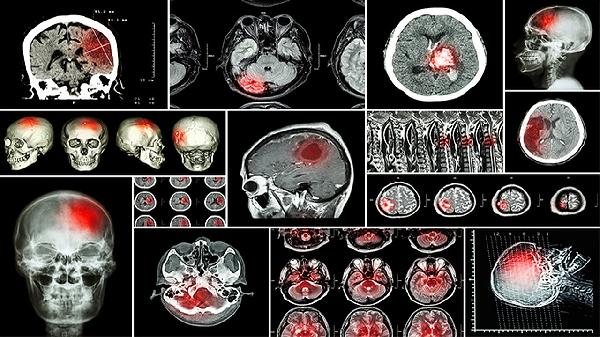

脑恶性肿瘤我们通常是根据患者的临床症状,以及头颅CT或者核磁共振等检查来初步判断,但是最终的确诊需要通过手术后病理检查,或者穿刺活检来明确诊断,并以此来制定患者术后下一步治疗方案颅内的恶性肿瘤,一般情况下通过核磁共振是可以检查出来的,核磁在肿瘤的诊断上分辨率要高一些,要优于CT,恶性肿瘤增长往往是比较快的,要在发现后的早期及时的进行治疗。脑癌是发生于颅内的恶性肿瘤。

脑癌晚期的患者病情会不断加重,会伴随着不断头疼且呕吐的情况出现,患者可以住院输水来进行治疗,不过只能够起到一定的的缓解效果。随着时间的推移,将导致视神经萎缩、视力丧失甚至失明,还会出现头晕和呼吸,包括血压等生命体征的变化。颅内的恶性肿瘤晚期常会引起严重的颅内压增高的症状。

一般情况下,脑肿瘤患者如果是在早期经过积极有效的治疗,可以达到治愈的,晚期有可能会出现癌细胞扩散,一起转移,容易引起栓塞,及时的到大型正规医院进行治疗祝您身体健康,万事如意。因而对于这种情况,还需要检查肝脏的功能变化情况,需要控制饮酒量,以避免造成酒精依赖综合症。颅内的恶性肿瘤,主要包括胶质瘤,恶性脑膜瘤以及转移瘤等。